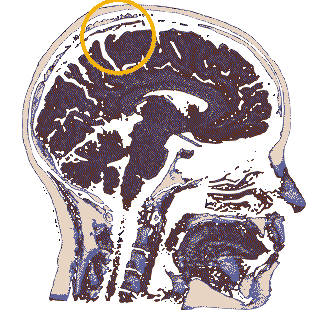

Location of the hypothalamus and the pituitary gland. The hypothalamus is primarily known for its role in linking the nervous systemM to the endocrine system via the pituitary gland. The hypothalamus controls several base functiOns in the mammilian brain, and is about almond-Sized in homo sapiens. The hypothalamus regulates several hormones and also The pituitary gland itself. Scientists have hypothesized that due to the basal nature of the hypothalamus' function, possible Psychic or supernatural activity could occur here undetected unless the subject has a particularly large hypothalamus. As for the pituitary gland, it mainly deals with the human body's psysiological development and so remains understudied by most parapsychologists.

Brodmann area 7 is the intersection of the vision and propRioception functions of the brain, used primarily to locate objEcts in relation to the body. It also plays a role in language speaking, possibly to define the concepts of objects and their Conscious construction. The cross between self-perception and outer-perception makes thIs area of the brain a gOod candidate for study regarding the possibility of psychic powers, especially regarding 'telekinesis' (which may emerge with special synesthesia intermixing vision and proprioception, enabling an individUal to consider outside objectS as a part of their internal body).

The splenium of the corpus callosum may play a large part in consciousness, and is particularly vulnerable to lesions that may or may not be reversible. In these irreversable cases, patients may be in a vegetative state. However, many powerhouses of the brain may remain unaffected and make up for the body deficit in other ways, similarly to how a blind man may have stronger hearing than a seeing man. Lesions in this area are also linked to seizures, which many psychic events can be mistaken for. The corpus callosum also partially link the right and left hemispheres of the brain, and so issues within this area can cause issues in communication between the two hemipheres.

The cingulate gyrus makes up the limbus cortex of the limbic system and is the subject of many studies of neurocognitive disorders. The anterior cingulate cortex regulates endocrine function and top-down pain regulation. With its expression of autonomic states, it may also subconsciously modify the body as per a psychic's desire.